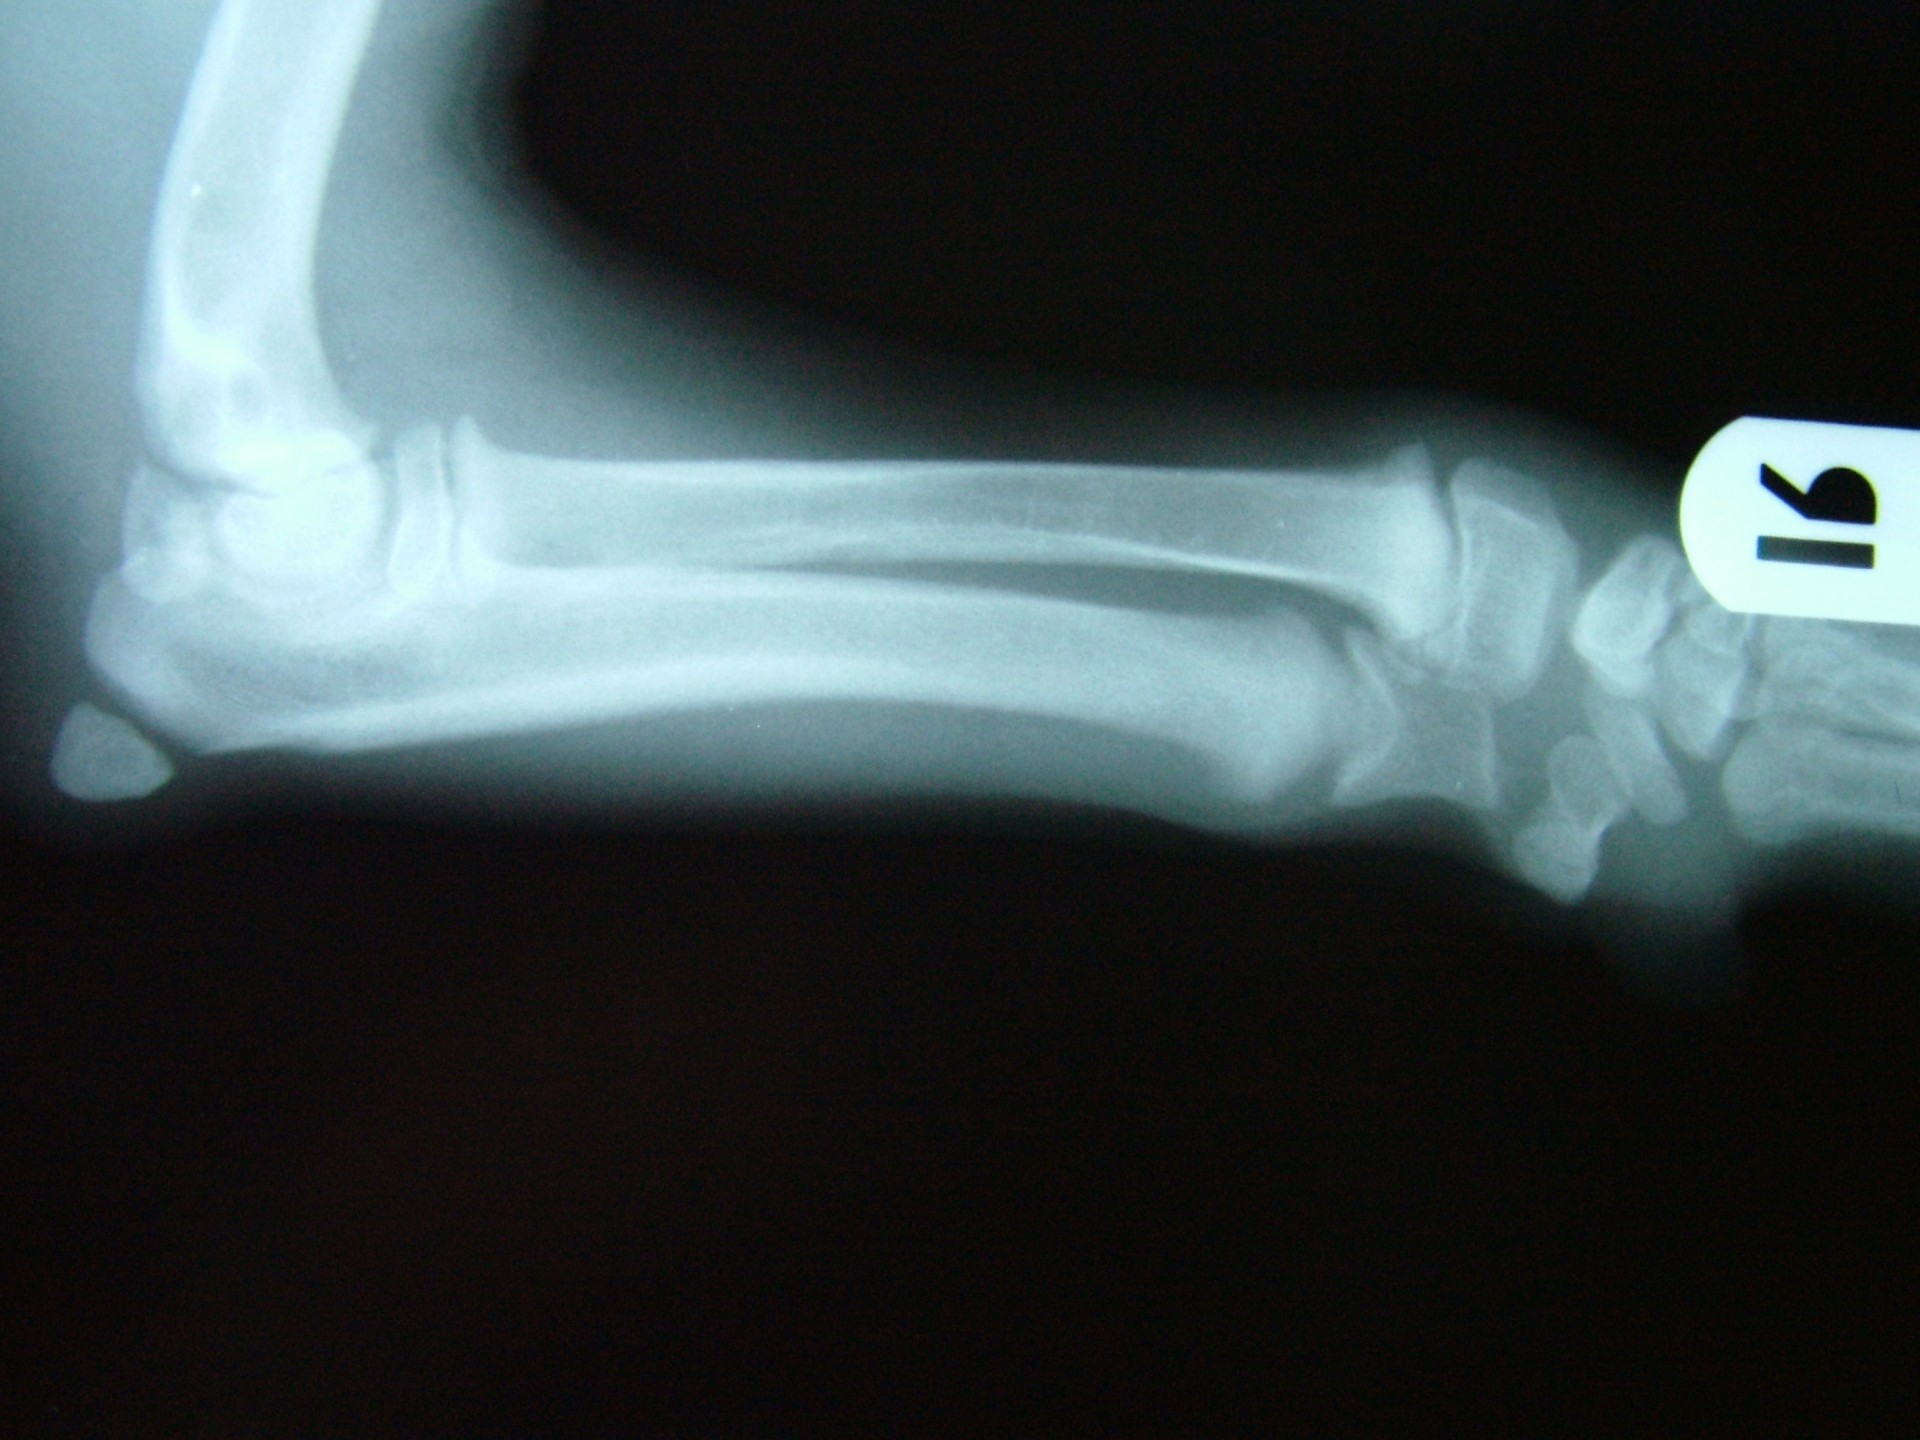

A betegségre jellemző, hogy az ébren klinikai tüneteket mutató állatok altatásban történő vizsgálata (az izmok ellazulása miatt)valamint az érintett végtagról készült röntgen vizsgálat mindig negatív eredménnyel zárul, a csontozatban rendellenesség nem mutatható ki.

A diagnózis felállítása során a legfontosabb, hogy kizárjuk a szintén fiatal állatokra jellemző, a csövescsontok növekedési zónájának lezáródásából adódó végtagdeformitást.